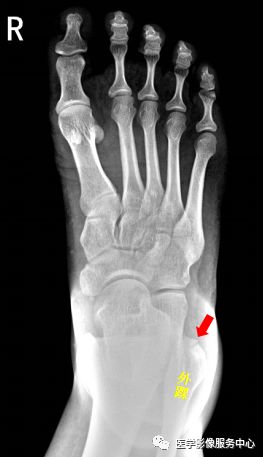

腕关节

图片

1.舟骨   2.月骨   3.三角骨   4.豌豆骨   5.大多角骨   6.小多角骨   7.头状骨   8.钩骨

右腕关节近三角骨、豆状骨内侧见多个游离骨碎片影,小碎骨片分离移位。考虑为,右腕关节三角骨,豌豆骨粉碎性骨折。

右侧桡骨远端可见不规则透亮骨折线,并累及关节面。右侧桡骨远端骨折

尺骨茎突见游离骨碎片影。右侧尺骨茎突骨折。